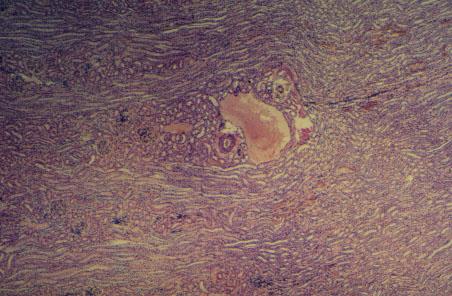

X-7 (4) Slide 85, Human Kidney (H&E). Low power view of the cortex-medullary area. Arcuate veins and medullary rays are seen.